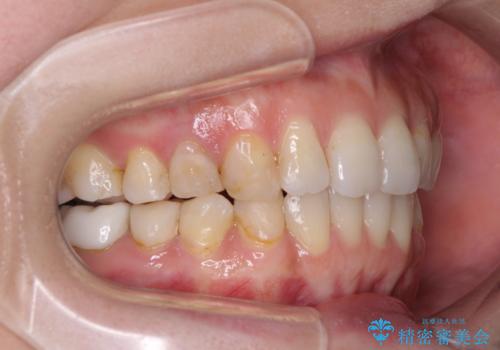

- 失活により変色した歯と不揃いな口元を気にして来院された患者様です。

口元をインビザラインにより歯列を整え、その後に失活している奥歯をオールセラミッククラウンにて補綴治療することとしました。